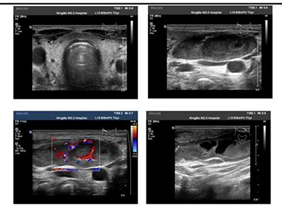

颈部超声:双侧颈部多发肿大淋巴结(最大者右侧 44×15mm,左侧 55×18mm),考虑为淋巴结核,部分液化。

颈部淋巴结活检:肉芽肿性病变伴坏死:抗酸染色(+ 弱阳性)、六胺银染色(-)、过碘酸 - 雪夫氏糖原染色(-),IgG(+), IgG4(+少量),IgG4/IgG<10%。